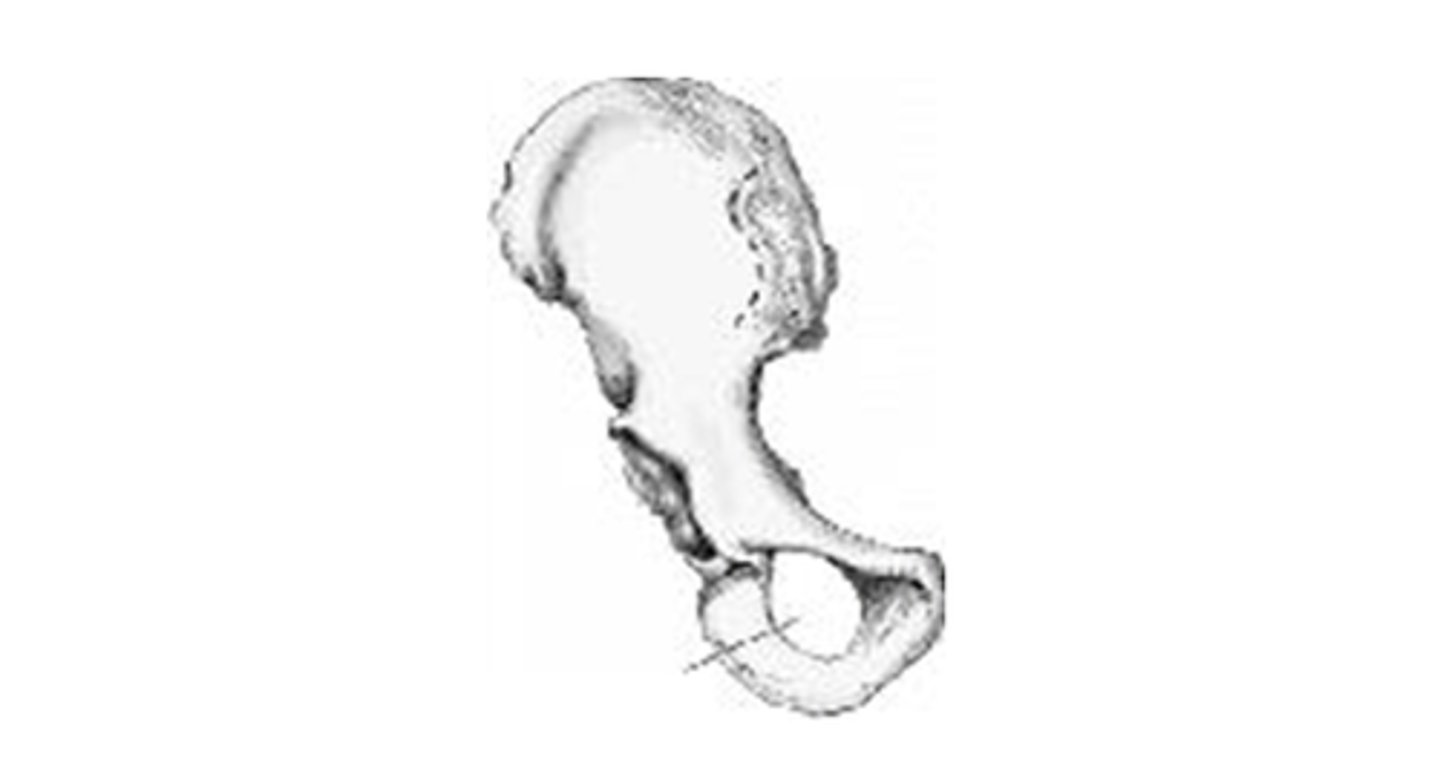

obturator foramen

anterior superior

intertrochanteric crest